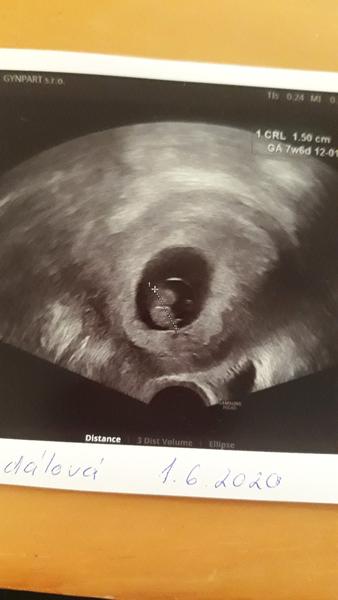

Holky jsem v 5. tydnu tehotenstvi 🥳🥳🥳 moc vam dekuji ze jste mi tady poradily a trochu uklidnily.

@lexa2000 Za 3 tydny jdu znovu 🙂 Uz byla videt mala kulicka ❤️❤️ Ale mam na vas jeste jeden dotaz, mam praci jako skladnik a tak tahat tezky veci apod a muj vedouci ki rekl ze se domluvi s tim nejvyssim jestli nebude lepsi si vybehat rizikove, ale ja cetla na netu ze podle zákona kdyz pro me nebude mit praci tak mi musi dat 100% a zustanu doma. Nevite nekdo o tomhle neco ? Dekuji 👍

Tak mám za sebou kontrolu a úplně se mi ulevilo. Mimco je zdravý, krásně mu bije srdíčko a vypadá že to bude bojovnice nebo bojovnik🥰 hned jak jsem přišla tak mi říkala že je možný že díky tomu krvácení tam třeba mimco už ani nebude a pak udělala ultrazvuk a řekla "Tyjo tak to jsem nečekala ani já 😂" prej za ty 2 týdny udělal obrovský pokrok 🥰